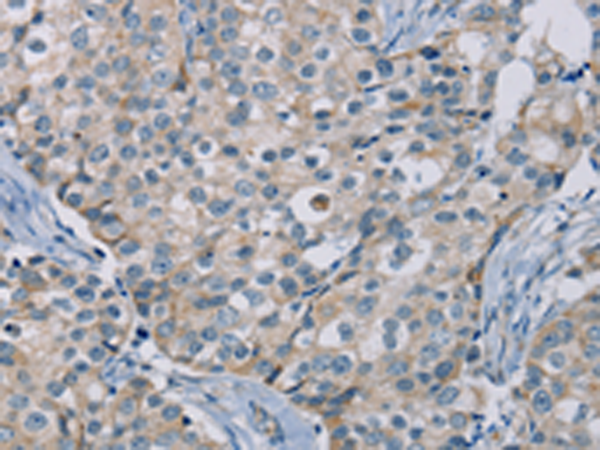

分类: 科研抗体货号: P08540别名: NOS2; ZC2HC12B应用: IHC反应种属: Human